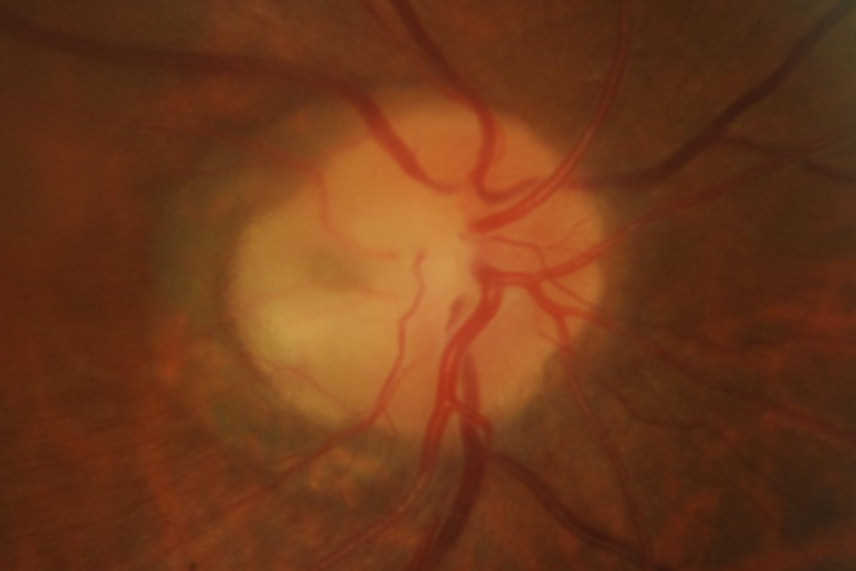

A 58-year-old male with no underlying medical history was referred for retinal oedema adjacent to the optic nerve head with cystic changes and a shiny appearance on the overlying retina for the right eye. Unaided visual acuity was 6/9 and 6/6. He was asymptomatic and was incidentally noted to have macula oedema during a routine examination. The anterior segment examination was normal, but the right eye optic disc assessment showed a greyish-white depressed area in the temporal quadrant (Figs 1 and 2) along with cystic changes at the macula. The left eye examination was normal. OCT examination of the right eye showed schisis-like separation of retinal layers, most marked in the outer retinal layers, extending up to the optic disc temporal margins (Fig 3). There appeared to be a clear communication between the optic disc and the schisis-like separation of outer retinal layers.

Clinically, ODP usually appears as a greyish-whitish, round or oval depression of the optic disc (Fig 1), and it may have different levels of severity. More than half of the patients in their third or fourth decade go on to develop maculopathy. Typically, OCT demonstrates fluid in the sub-retinal and intra-retinal compartments. The outer retinal layers are more commonly affected and the OCT demonstrates schisis-like separation of the outer retinal layers. Very often, schisis-like separation of the retinal layers extends to the optic disc pit, as seen in this case.